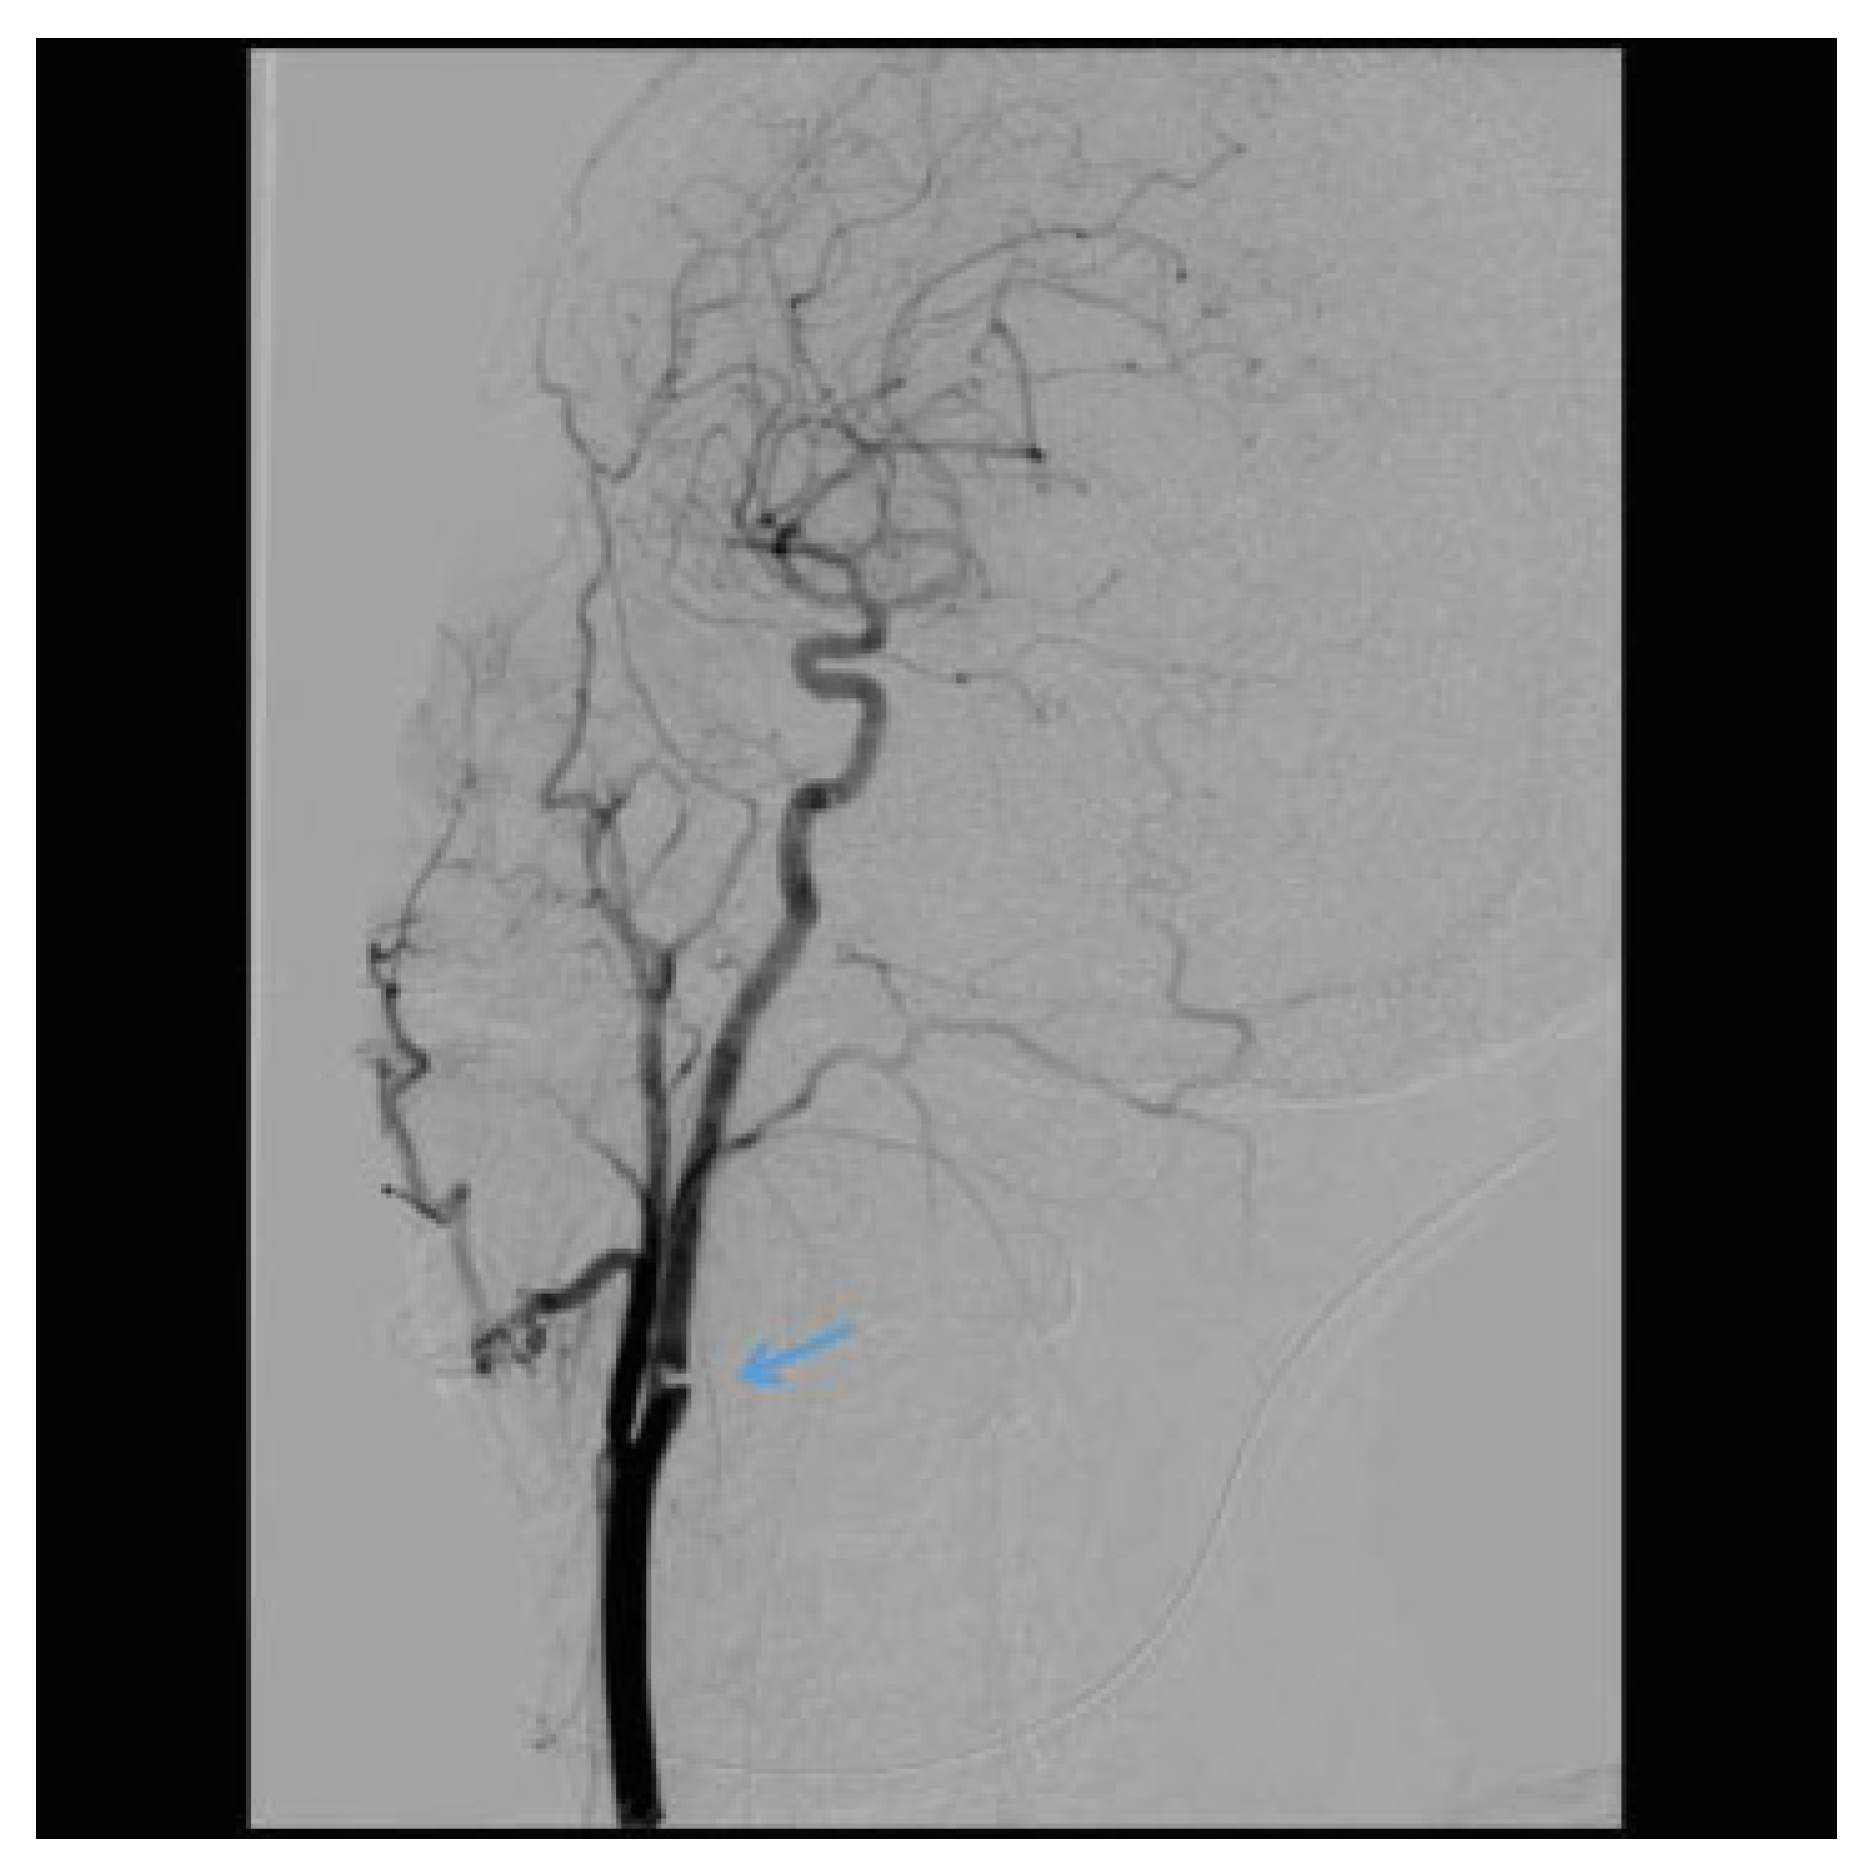

Penetrating Extracranial Carotid Artery Trauma

Intracranial Carotid Artery Trauma